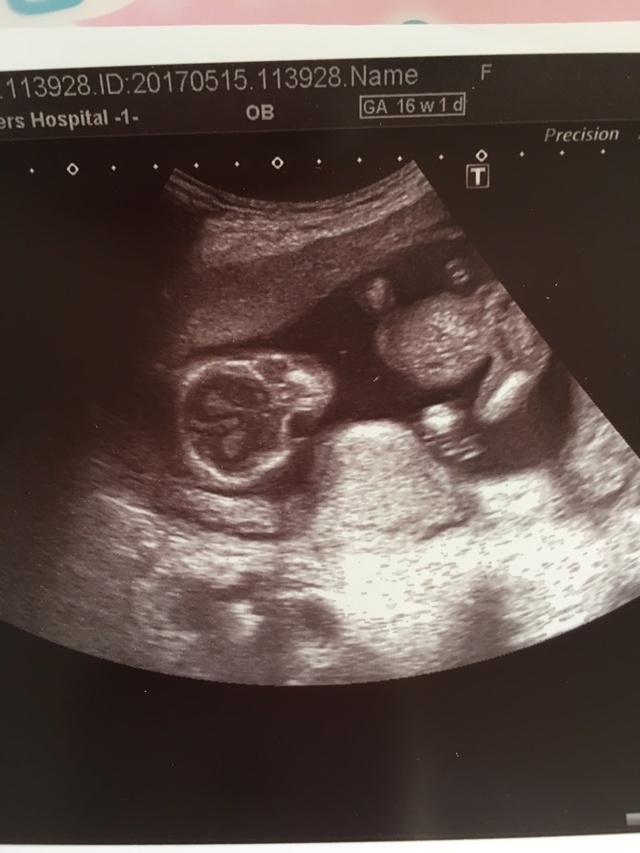

16週1日(16w1d・性別不明)|Yukiiii25 さん(26歳)

エコー写真撮影時のエピソード:

エコー写真を撮るたびに成長している赤ちゃんに感動します♡たったの2週間でも大きくなってるのがわかるし最近は4週間に一回になってしまって少し寂しいですが胎動がわかるようになり、早く会いたい♡と思うようになりました。

家族とエコー写真をみて手だ!足だ!など合ってるかわからないけど、みんなで話すのが楽しいです!次の健診で性別がわかると先生に言われましたので性別がわかったらベビー用品を揃えていきたいとおもってます。